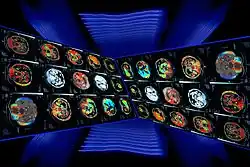

Dans les appareils modernes, l'émetteur de rayons X (tube à rayons X) effectue une rotation autour du patient en même temps que les récepteurs situés en face, et qui ont pour fonction de mesurer l'intensité des rayons après qu'ils ont été partiellement absorbés durant leur passage à travers le corps. Les données obtenues sont ensuite traitées par ordinateur, ce qui permet de recomposer des vues en coupes bidimensionnelles puis des vues en trois dimensions des organes. On peut faire ressortir le contraste de certains tissus, en particulier des vaisseaux sanguins, en injectant un produit dit « de contraste » (un complexe de l'iode) qui a la propriété de fortement absorber les rayons X et donc de rendre très visibles les tissus où ce produit est présent (qui apparaissent alors hyperdenses, c'est-à-dire plus « blancs » sur l'image). Grâce aux tomodensitomètres multidétecteurs (ou multi-barrettes) à acquisition spiralée (déplacement lent de la table d'examen durant l'acquisition), on obtient depuis les années 1990 une exploration très précise d'un large volume du corps humain pour un temps d'acquisition de quelques secondes.

Durant l'acquisition, les images sont visualisées sur une console informatique par le manipulateur en électroradiologie médicale et par le médecin radiologue.

Simultanément, le radiologue reçoit sur sa console de visualisation et de traitement l'ensemble des données acquises (de 150 à plus de 2 000 images).

Celles-ci se présentent sous la forme de « coupes » ou tranches d'épaisseur millimétrique (de 0,4 mm à 10 mm) que le radiologue peut étudier dans tous les plans de l'espace (sagittal, axial, coronal et obliques), et qu'il s'agit de post-traiter (augmentation de l'épaisseur des coupes visualisées, mise en valeur de certaines densités, reconstructions volumiques en 3D, extraction des vaisseaux ou des structures osseuses, navigation virtuelle endoscopique, etc.).